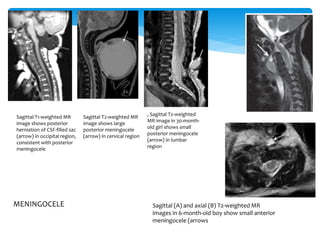

Sagittal T1-weighted MR

image shows posterior

herniation of CSF-filled sac

(arrow) in occipital region,

consistent with posterior

meningocele

Sagittal T2-weighted MR

image shows large

posterior meningocele

(arrow) in cervical region

, Sagittal T2-weighted

MR image in 30-month-

old girl shows small

(arrow) in lumbar

region

Sagittal (A) and axial (B) T2-weighted MR

images in 6-month-old boy show small anterior

meningocele (arrows